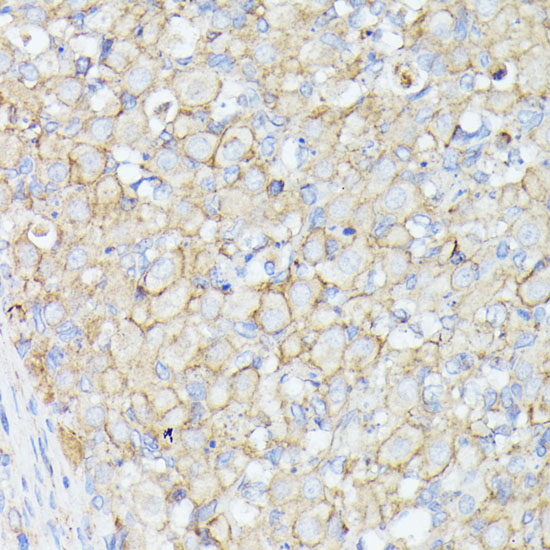

ApplicationWB, IHC; Recommended dilution: WB 1:200 - 1:1000, IHC 1:50 - 1:100